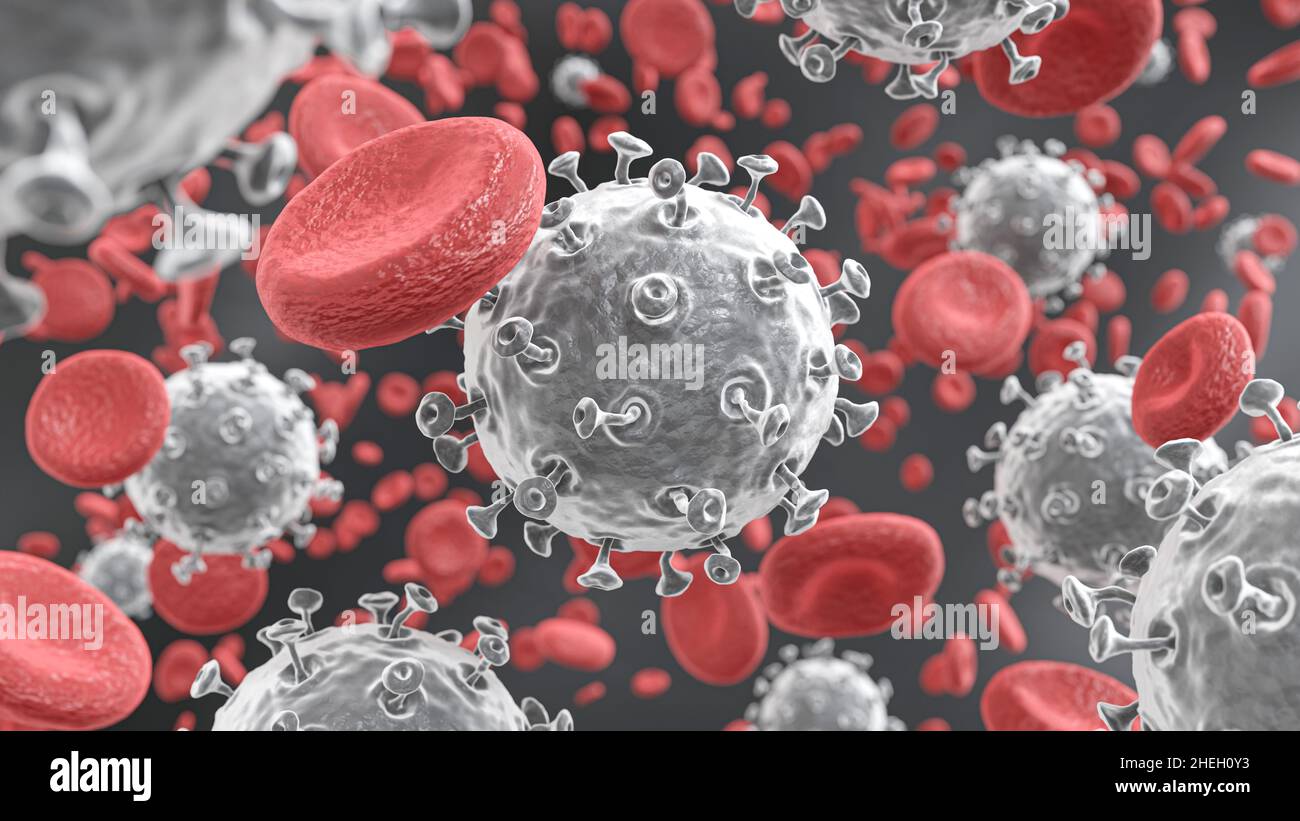

COVID19 Corona virus with spike glycoprotein are floating on bloodstream with red blood cells in vascular . 3D rendering . Stock Photohttps://www.alamy.com/image-license-details/?v=1https://www.alamy.com/covid19-corona-virus-with-spike-glycoprotein-are-floating-on-bloodstream-with-red-blood-cells-in-vascular-3d-rendering-image456448695.html

COVID19 Corona virus with spike glycoprotein are floating on bloodstream with red blood cells in vascular . 3D rendering . Stock Photohttps://www.alamy.com/image-license-details/?v=1https://www.alamy.com/covid19-corona-virus-with-spike-glycoprotein-are-floating-on-bloodstream-with-red-blood-cells-in-vascular-3d-rendering-image456448695.htmlRF2HEH0Y3–COVID19 Corona virus with spike glycoprotein are floating on bloodstream with red blood cells in vascular . 3D rendering .